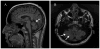

Results: Two variants were identified in SLC25A46. Mutations in this gene have been previously associated with Charcot-Marie-Tooth type 2 and optic atrophy. While the previously reported variant p.Arg340Cys seems to be consistently associated with the same clinical features such as childhood onset, optic atrophy, gait and speech difficulties, and wasting of the lower limbs, the patient with the novel mutation p.Trp160Ser did not present with optic atrophy and his ocular abnormalities were limited to nystagmus and saccadic pursuit.